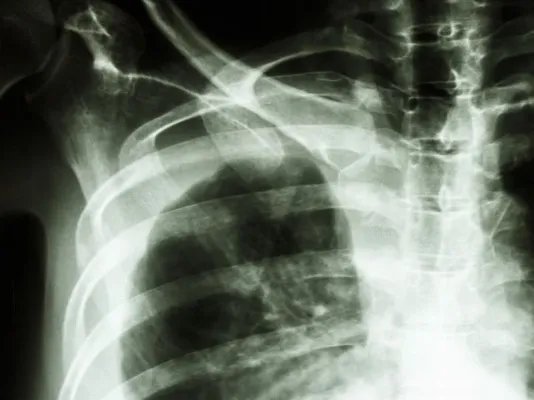

肺癌复发症状

的有关信息介绍如下:肺癌术后出现复发,就是说在患者做了手术的部位又出现了新的癌组织,肺癌复发症状与原发性肺癌相似,以癌肿对周围组织的压迫症状为主,可出现咳嗽、咳痰、胸闷、咯血、胸痛等表现。